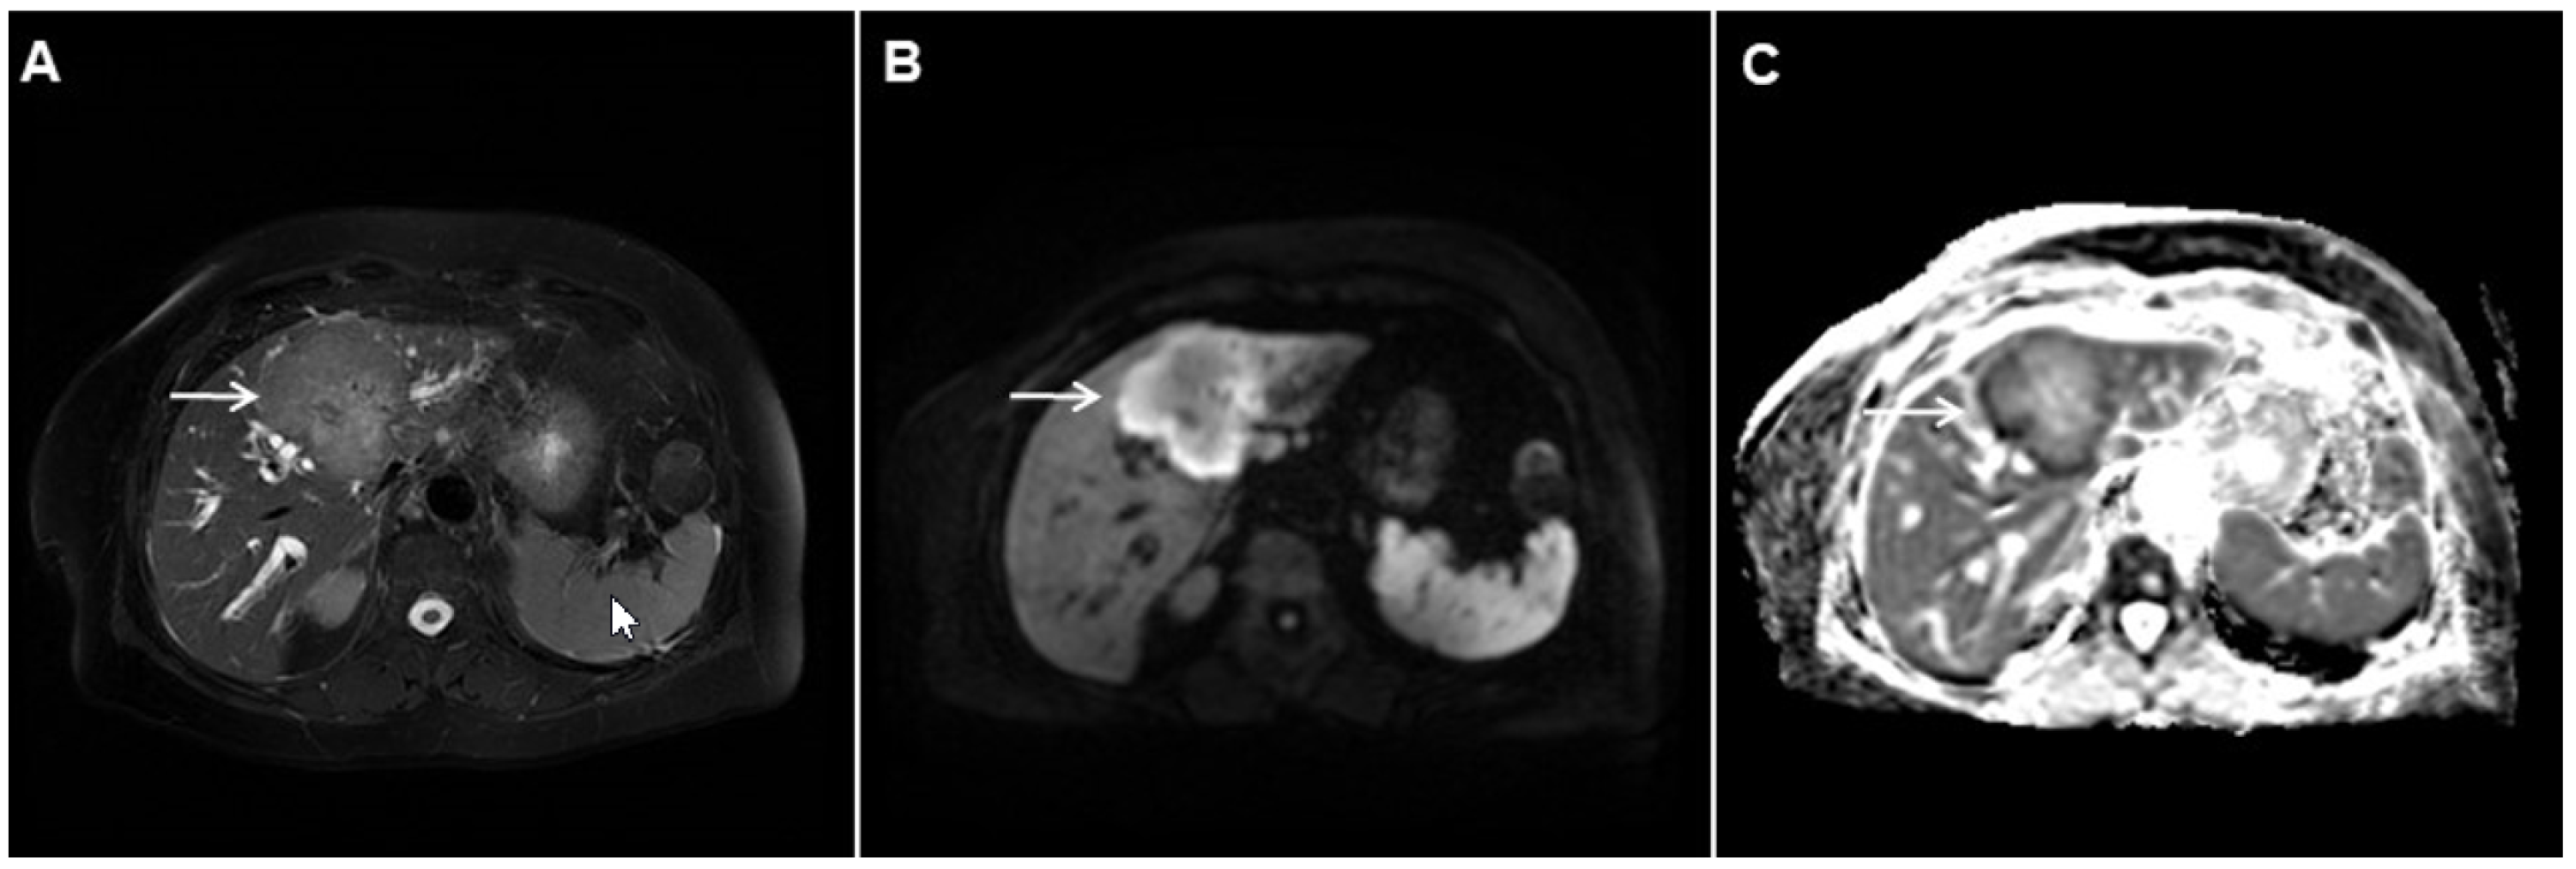

2.1. Typical Imaging Features of mICC

2.2. Atypical Imaging Features of mICC